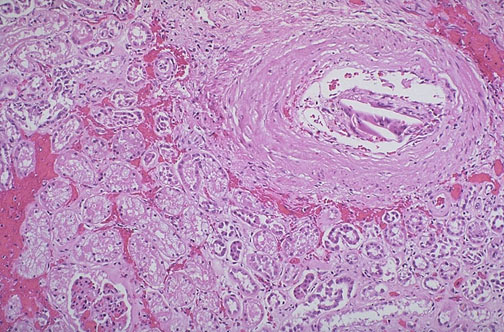

| Despite the frequency of aortic atherosclerosis, cholesterol emboli are rare, or at least clinically insignficant most of the time. Seen here in a renal artery branch are cholesterol clefts of such an embolus. This patient had severe ulcerative, friable atheromatous plaques and had undergone angiography, which increases the risk for such emboli. |